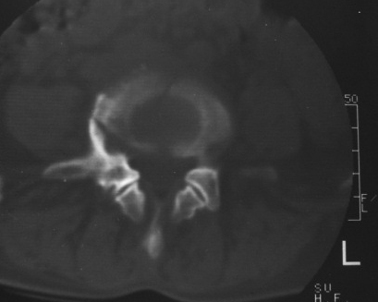

以下是引用gaoxiao在2007-3-1 18:02:00的发言:[br]腰5骶1椎体见骨质破坏,其内见死骨形成,椎前软组织肿胀,感染性病变,腰骶椎tb。

以下是引用gaozhengyi在2007-3-1 19:39:00的发言:[br]骨质破坏并砂砾样死骨为椎体结核的表现。椎体结核骨质破坏区的特点是呈虫蚀状,常可见硬化缘。死骨表现为片状高密度影,正如本例。

以下是引用织梦在2007-3-1 21:17:00的发言:[br]腰5椎体骨质碎裂,密度增高,边缘较毛糙,椎体内可见一斜行透亮线及骨质硬化,周围软组织肿胀不明显。本人认为还应该再仔细询问病史,看是否有外伤史。这个病例我考虑腰5椎体陈旧性骨折继发感染可能。